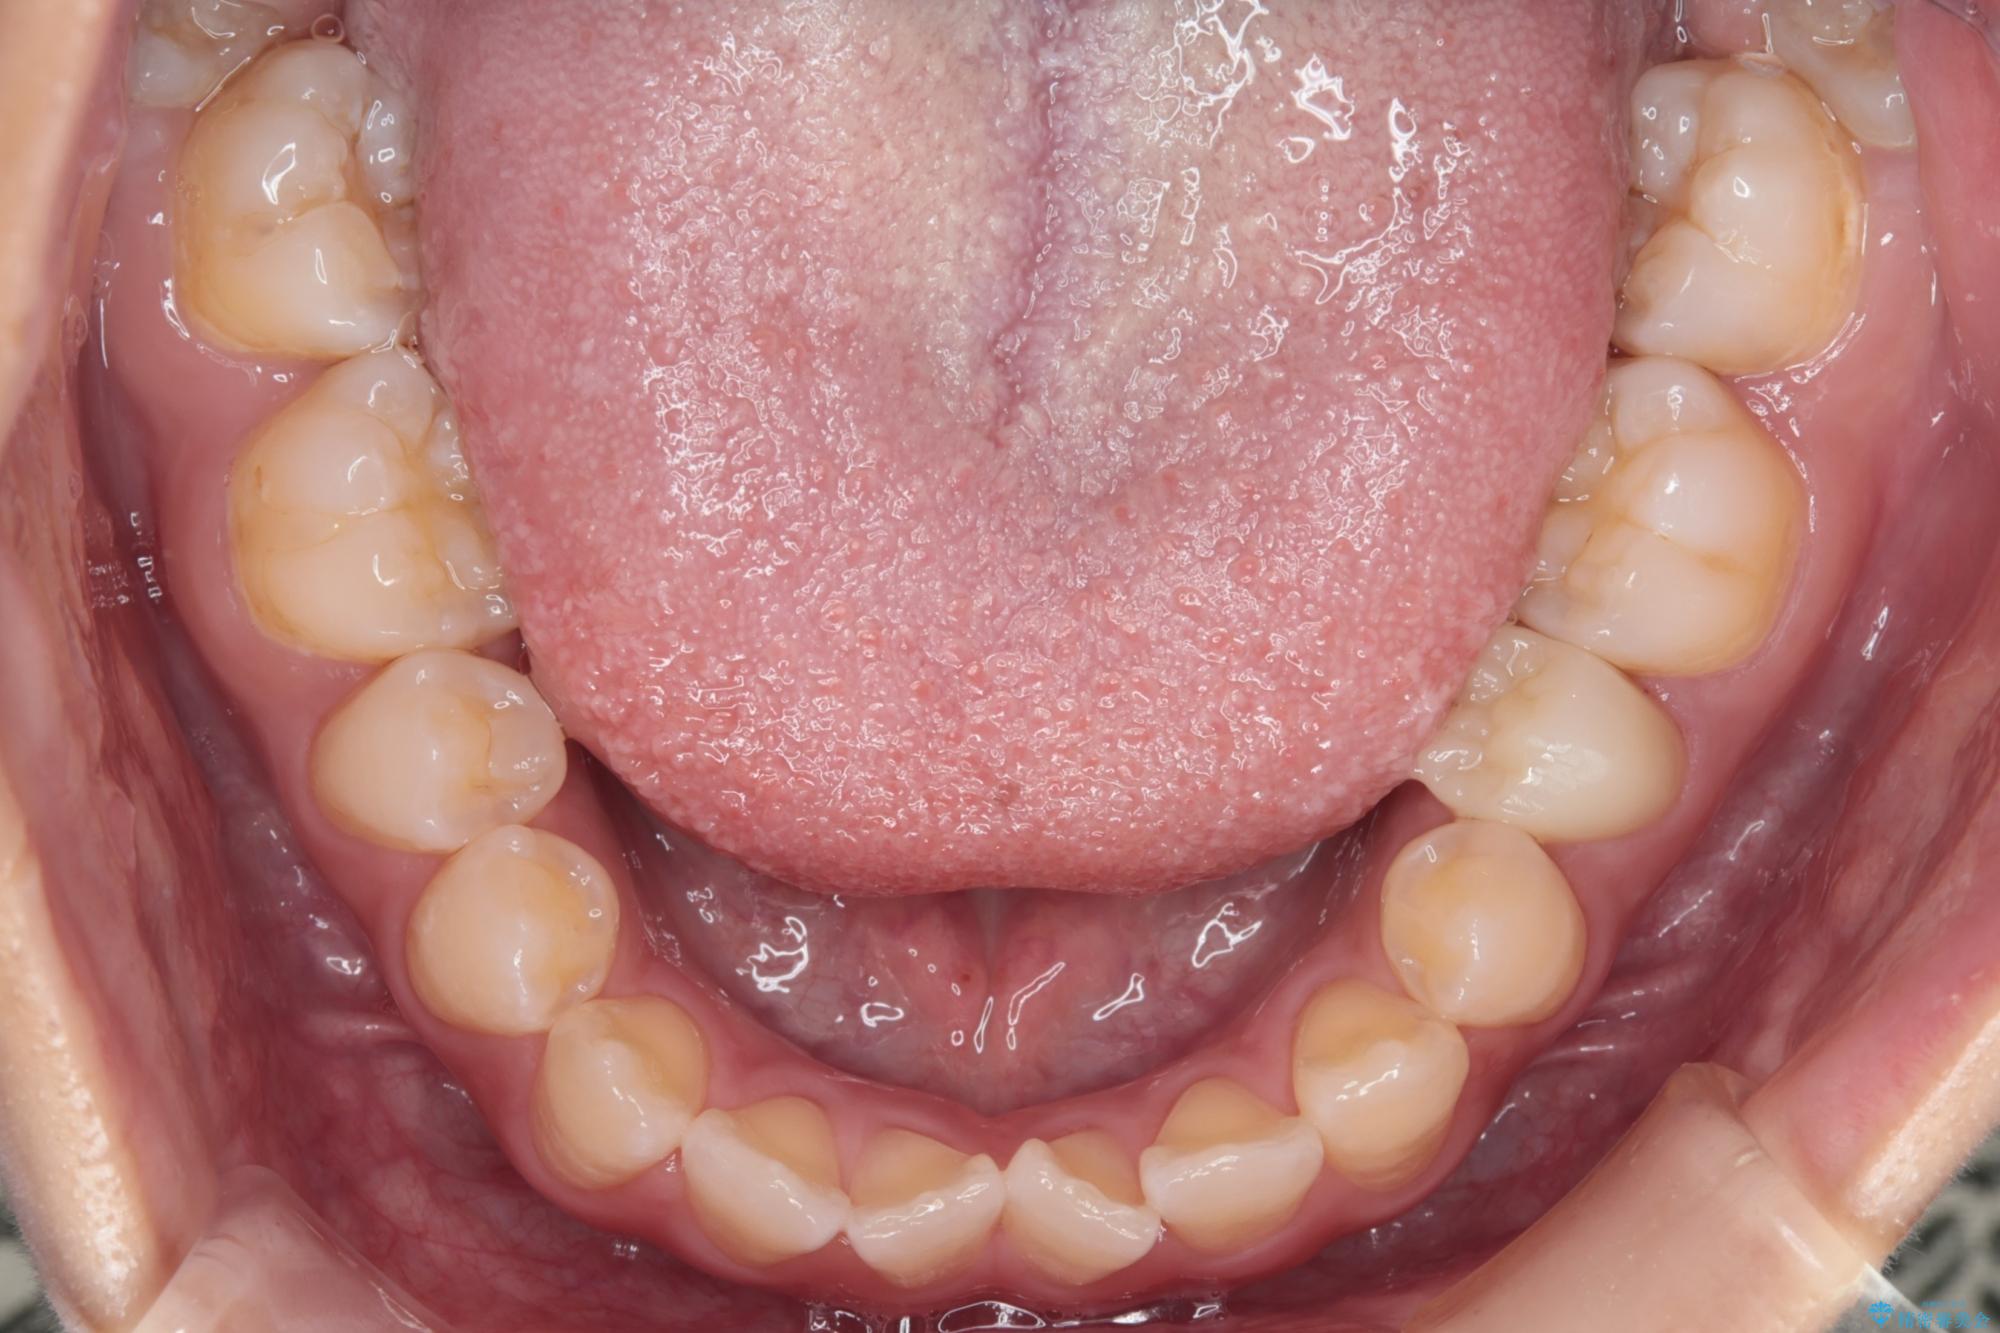

予定通り1年で気になっていた八重歯とガタつきが改善され、大変喜んでいただけました。